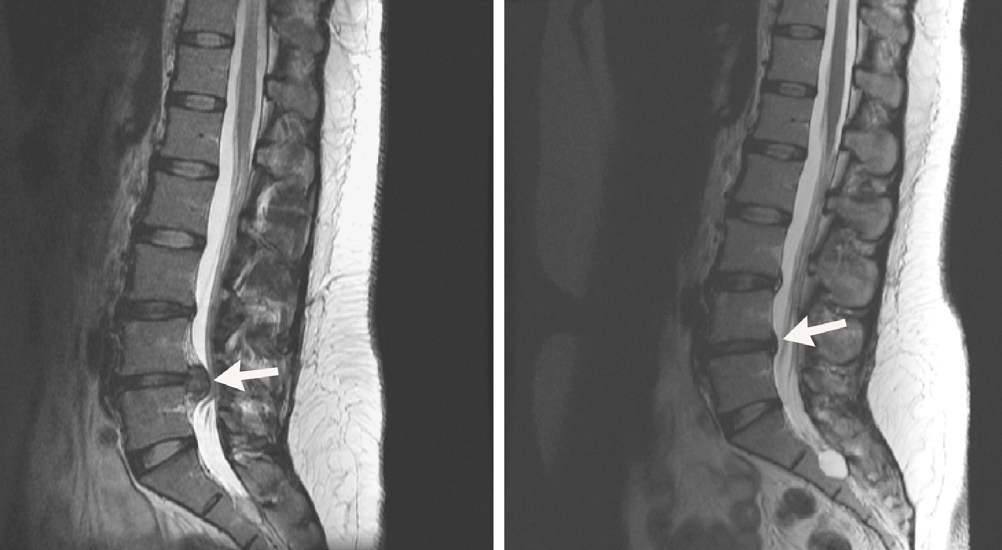

Körpereigener Wirkstoff lässt Bandscheibenvorfall schrumpfen DPV

Körpereigener Wirkstoff lässt Bandscheibenvorfall schrumpfen DPV Pda Trotz Bandscheibenvorfall Die periduralanästhesie (pda oder auch epiduralanästhesie) ist ein verfahren zur betäubung von rückenmarksnerven. Wenn ein bandscheibenvorfall im lendenwirbelbereich beschwerden verursacht, reicht meist eine konservative behandlung aus. Dazu gehören die rückenmarksnahen anästhesieverfahren spinalanästhesie und periduralanästhesie (pda). Peridurale anästhesie (pda) bei erkrankungen, bei denen es zu einem reizungszustand der nerven innerhalb des wirbelkanals kommt, kann eine pda durchgeführt werden. Spinalanästhesie (spa) oder. Pda Trotz Bandscheibenvorfall.